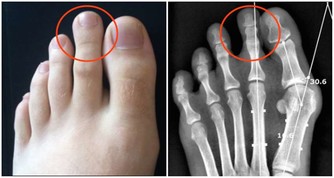

太衝穴是人體重要穴位之一,在腳背上,第一、二蹠骨結合部之前凹陷處,它是肝經的原穴和腧穴,所以也被有的朋友稱為人體的“出氣筒”,能夠很好的調動肝經的元氣,去肝火,解肝鬱,效果實在太好了。